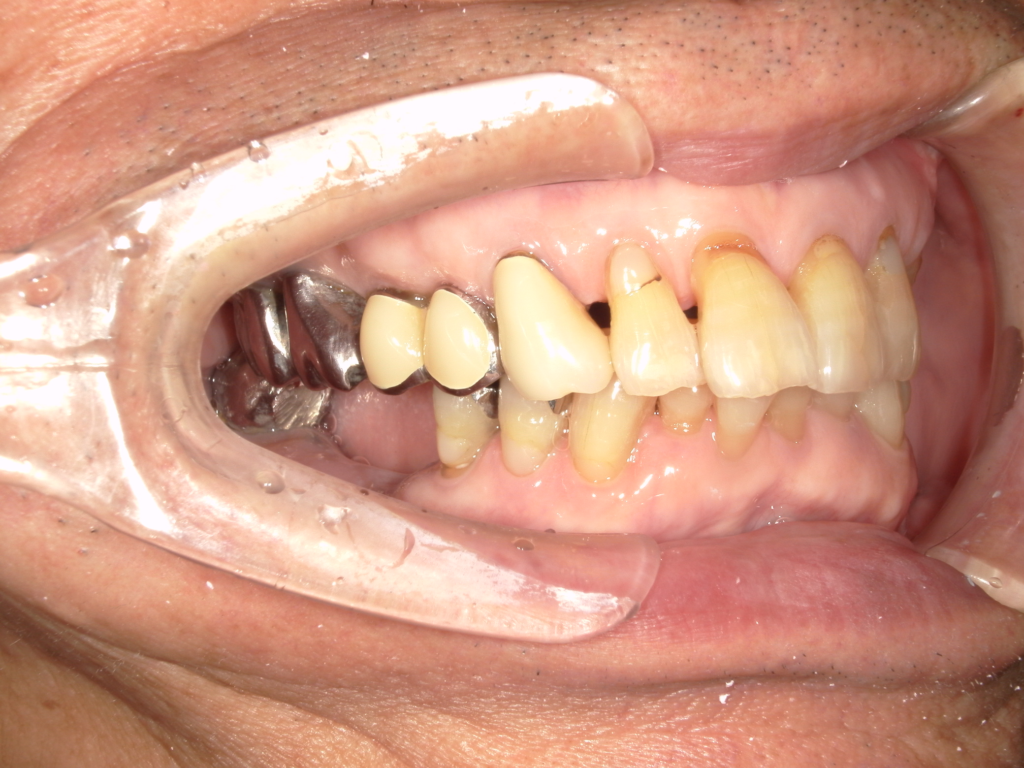

Y様インプラント実例 #44

左の上下の奥歯をインプラントで治療しています。

左下の奥歯は歯を抜くのと同時にインプラントの埋め込みを行っています。

被せものは上下、セラミックスで作っています。

治療前

治療後